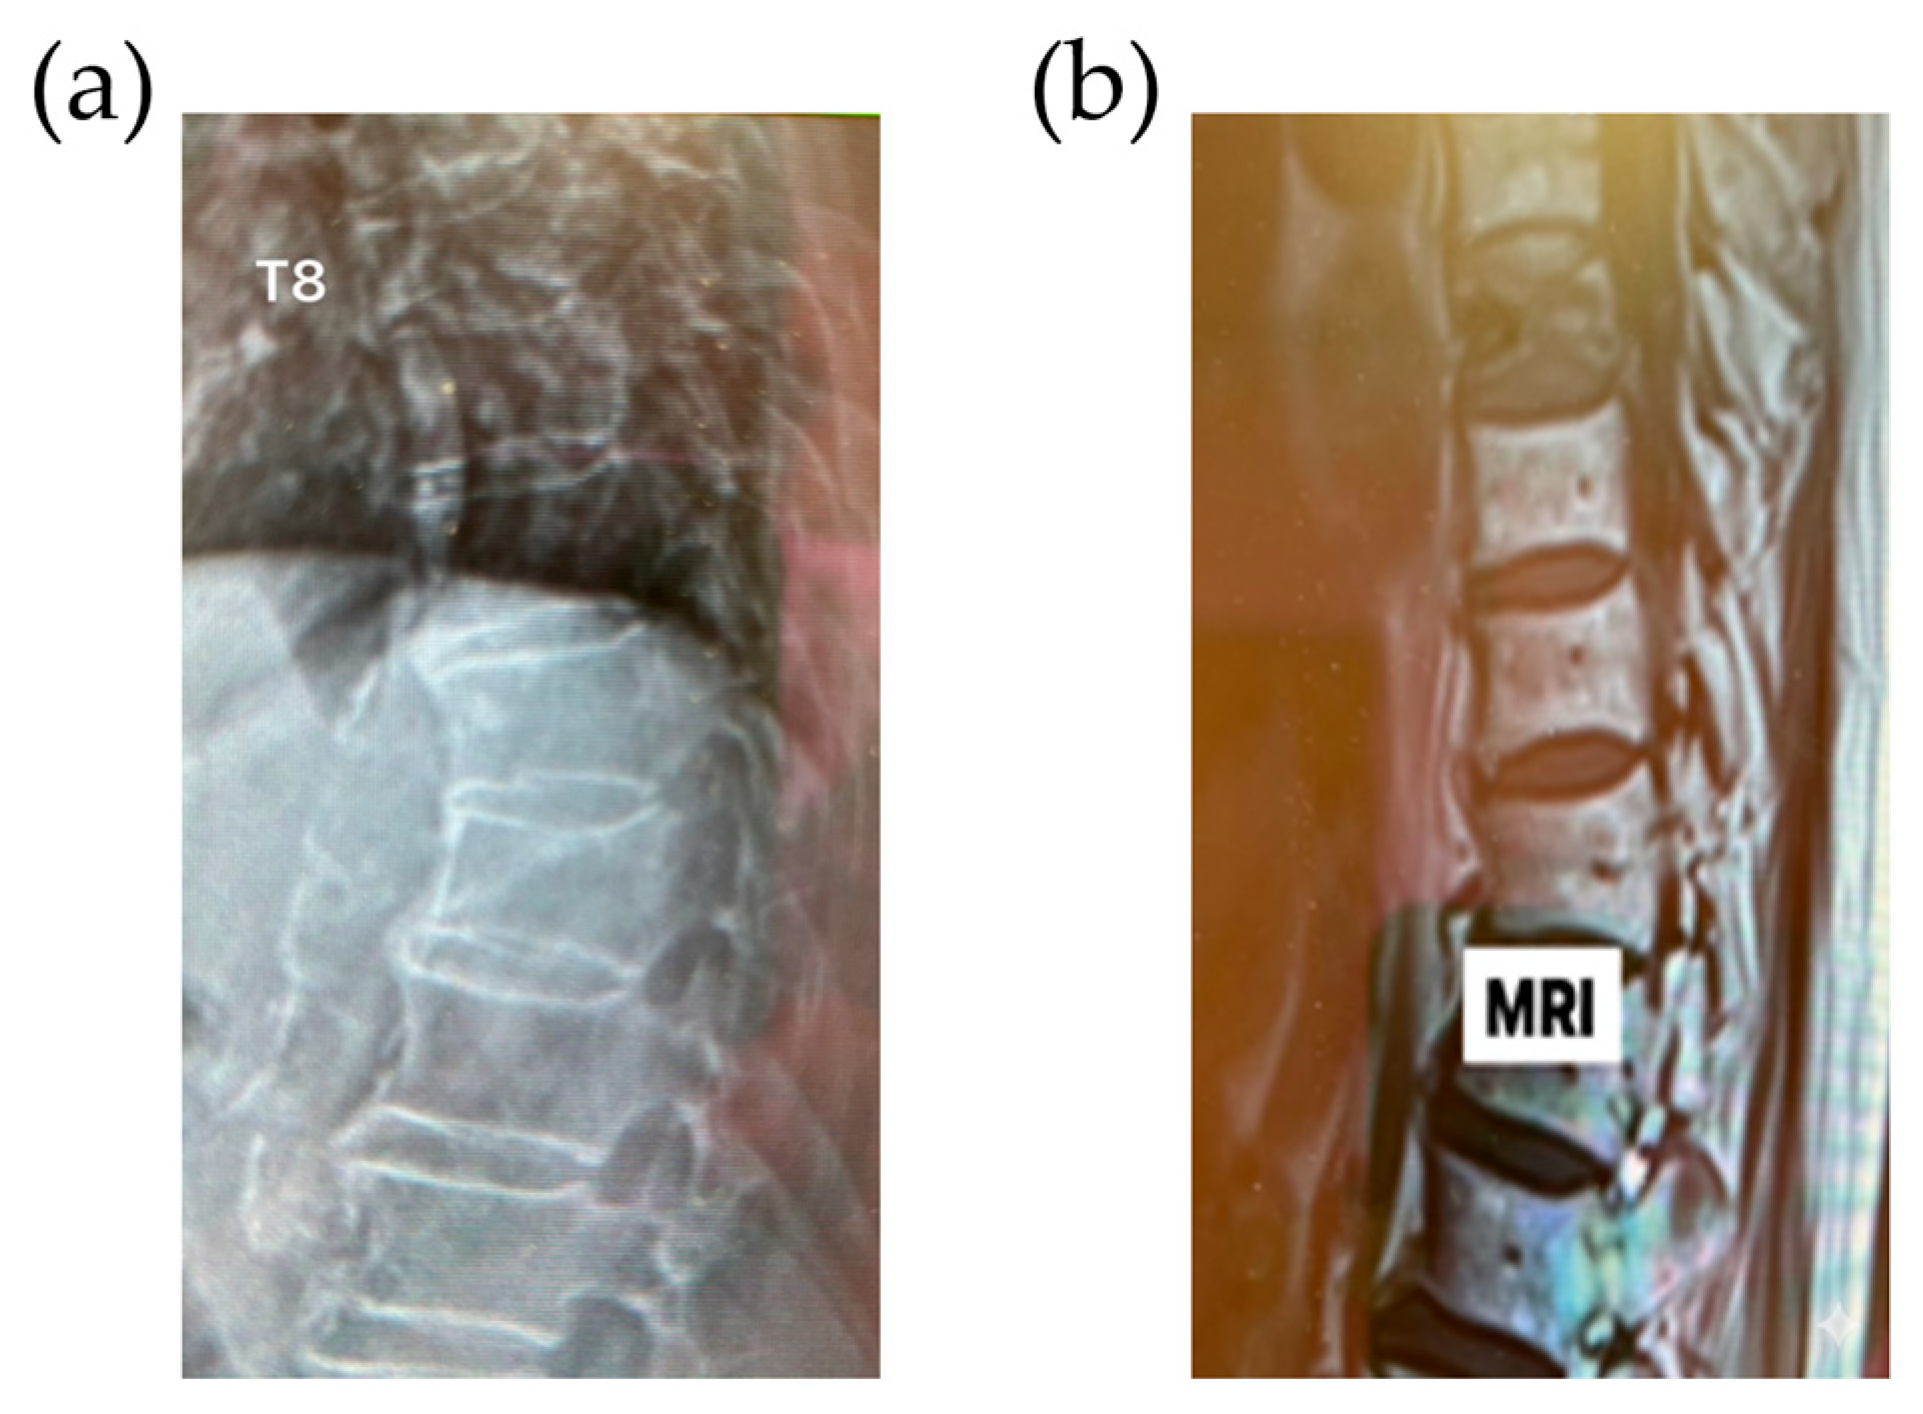

2.1. Patient History and Evaluation

2.2. Surgical Technique